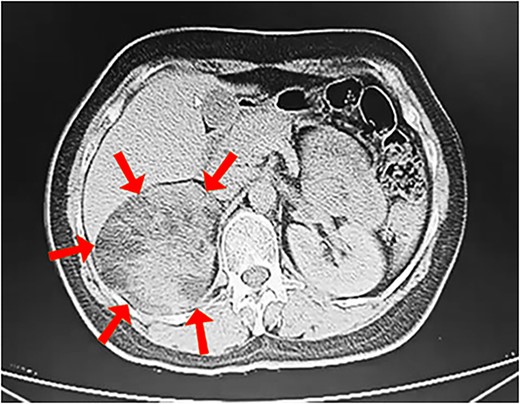

We report the case of a 45-year-old female, who presented to our hospital because of a mass on the right adrenal gland that was discovered incidentally during a periodic echocardiogram without any symptoms on the patient. The patient declared a history of excisional biopsy for a benign breast mass, a medical history of medication-controlled hypertension for 5 years, and Type 2 diabetes for 10 years but the family history was unremarkable. Laboratory investigations, including complete blood count and biochemical markers, were within normal limits. Imaging studies were performed, including contrast-enhanced computed tomography (CT) of the abdomen. The CT scan revealed a large, well-defined, heterogeneous mass measuring 13 × 12 × 9.5 cm, located in the right adrenal gland. The mass contained areas of high attenuation, suggesting recent hemorrhage, along with fat-density areas consistent with adipose tissue (Fig. 1). There were no signs of invasion into adjacent structures or lymphadenopathy. Based on the clinical presentation and radiological findings, the provisional diagnosis was a hemorrhagic giant adrenal myelolipoma. The patient underwent a right open adrenalectomy to address a large mass and minimize potential complications such as hemorrhage. Intraoperatively, a large, encapsulated mass was found in the right adrenal gland. The mass was carefully dissected from surrounding tissues, and the adrenal gland was removed and sent to the pathology department. There were no intraoperative complications. Upon gross examination, a mass with a total weight of 44.5 g was observed, measuring 15 × 10.5 × 5 cm. The mass displayed encapsulation and exhibited a rubbery to cystic consistency, with areas of hemorrhage evident. The cut surface revealed a heterogeneous composition, ranging in color from yellow to black and presenting a gelatinous texture. Multiple sections of the specimen were subsequently submitted for further analysis (Fig. 2). Microscopic examination revealed a mixture of mature adipose tissue and hematopoietic elements, including myeloid and erythroid cells. Focal areas of hemorrhage and hemosiderin deposits were observed within the tumor (Fig. 3), consistent with the radiological findings. Histopathological examination confirmed the diagnosis of a hemorrhagic adrenal myelolipoma. There was no evidence of malignancy. The patient had an uneventful postoperative recovery and was discharged on the 5th day after surgery. Follow-up at 6 months showed no complications, and imaging studies demonstrated no evidence of tumor recurrence. The patient continues to be asymptomatic and is under regular surveillance.

Contrast-enhanced CT scan showing a heterogeneous mass measuring 13 × 12 × 9.5 cm in the right adrenal gland (arrows).